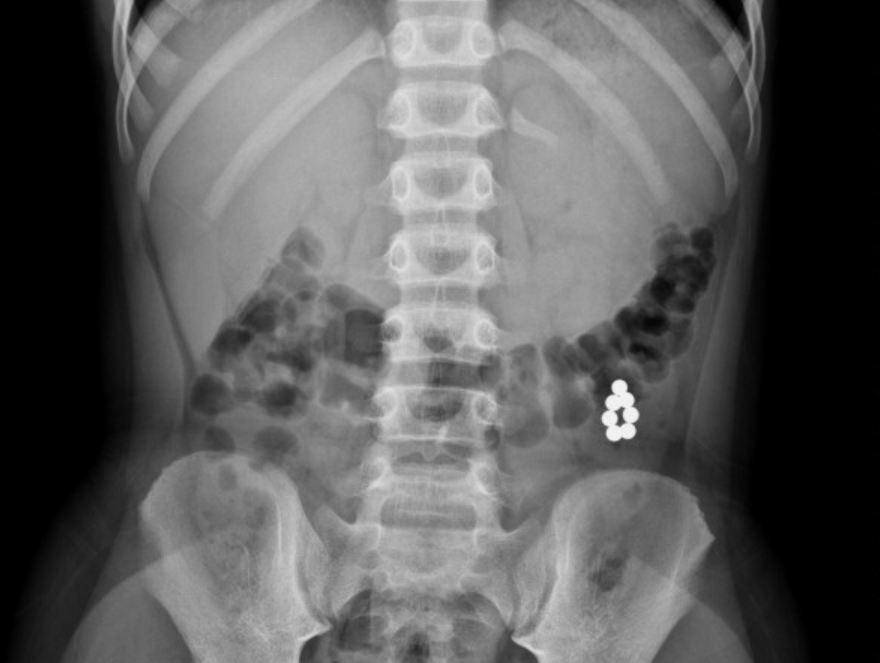

去年6月,一位医生发了一条朋友圈,配图瞬间炸锅了:这是一个6岁男孩的X光片,其中最惹人注意的就是肚子那块儿的“项链”。

但事实上,这根本就不是项链,而是29颗磁力珠连成了串!

到医院的时候,男孩已经腹痛了两天,家长以为是普通的肠炎,就给孩子吃益生菌助消化。在没有产生效果后,就跑到了医院。

接诊的医生一眼就看出了肠穿孔,要求立即做全麻手术。一个半小时后,才把29颗磁力珠从孩子体内取了出来。

2018年,青岛一个11岁男孩吞掉了21颗磁力珠,靠着磁力的互吸,也串在了一起: